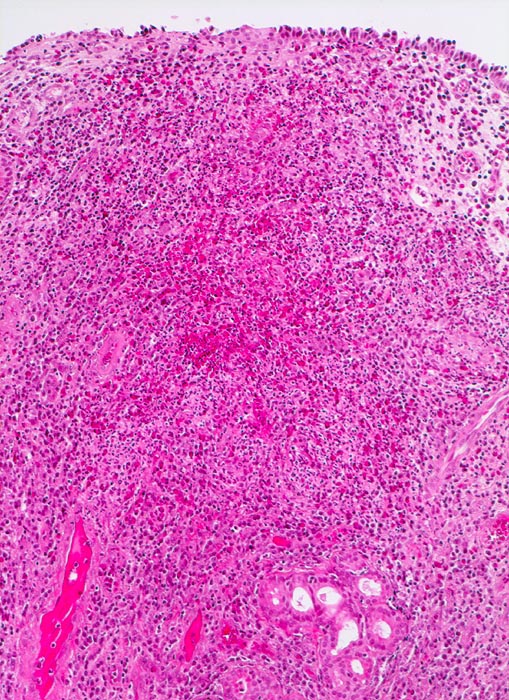

Morphologische Merkmale:

• Polypoides Gewebsfragment bedeckt von mehrreihigem Flimmerepithel.

• Herdförmige Schleimhauterosionen.

• Ödematöses Stroma mit gemischtem Entzündungsinfiltrat: Lymphozyten, Plasmazellen, Histiozyten und zahlreiche eosinophile Granulozyten.

• Im Zentrum des Polypen Drüsenläppchen und zahlreiche Blutgefässe.